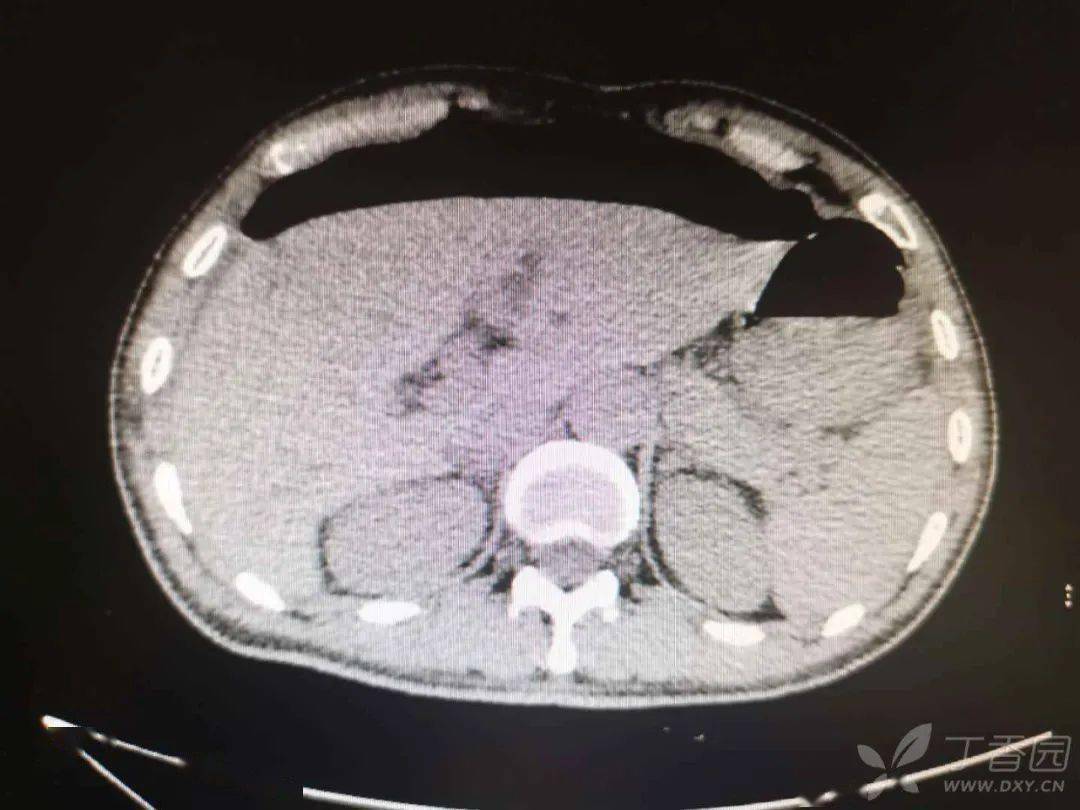

消化道穿孔的ct诊断